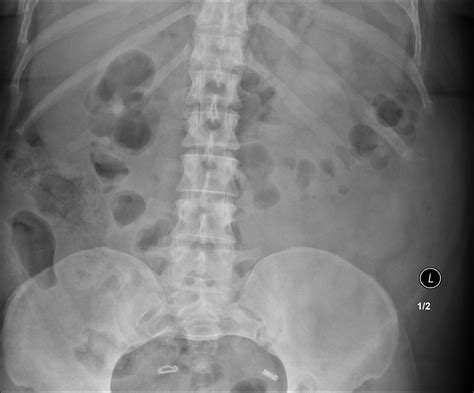

Common Findings in a Normal Abdominal X Ray

A Normal Abdominal X Ray typically reveals the following structures and patterns:

• Gas patterns in the stomach and intestines

• Clear outlines of the liver, spleen, and kidneys

• No signs of obstruction or perforation

• No evidence of foreign bodies

These findings indicate that the abdominal organs are functioning normally and there are no immediate concerns.